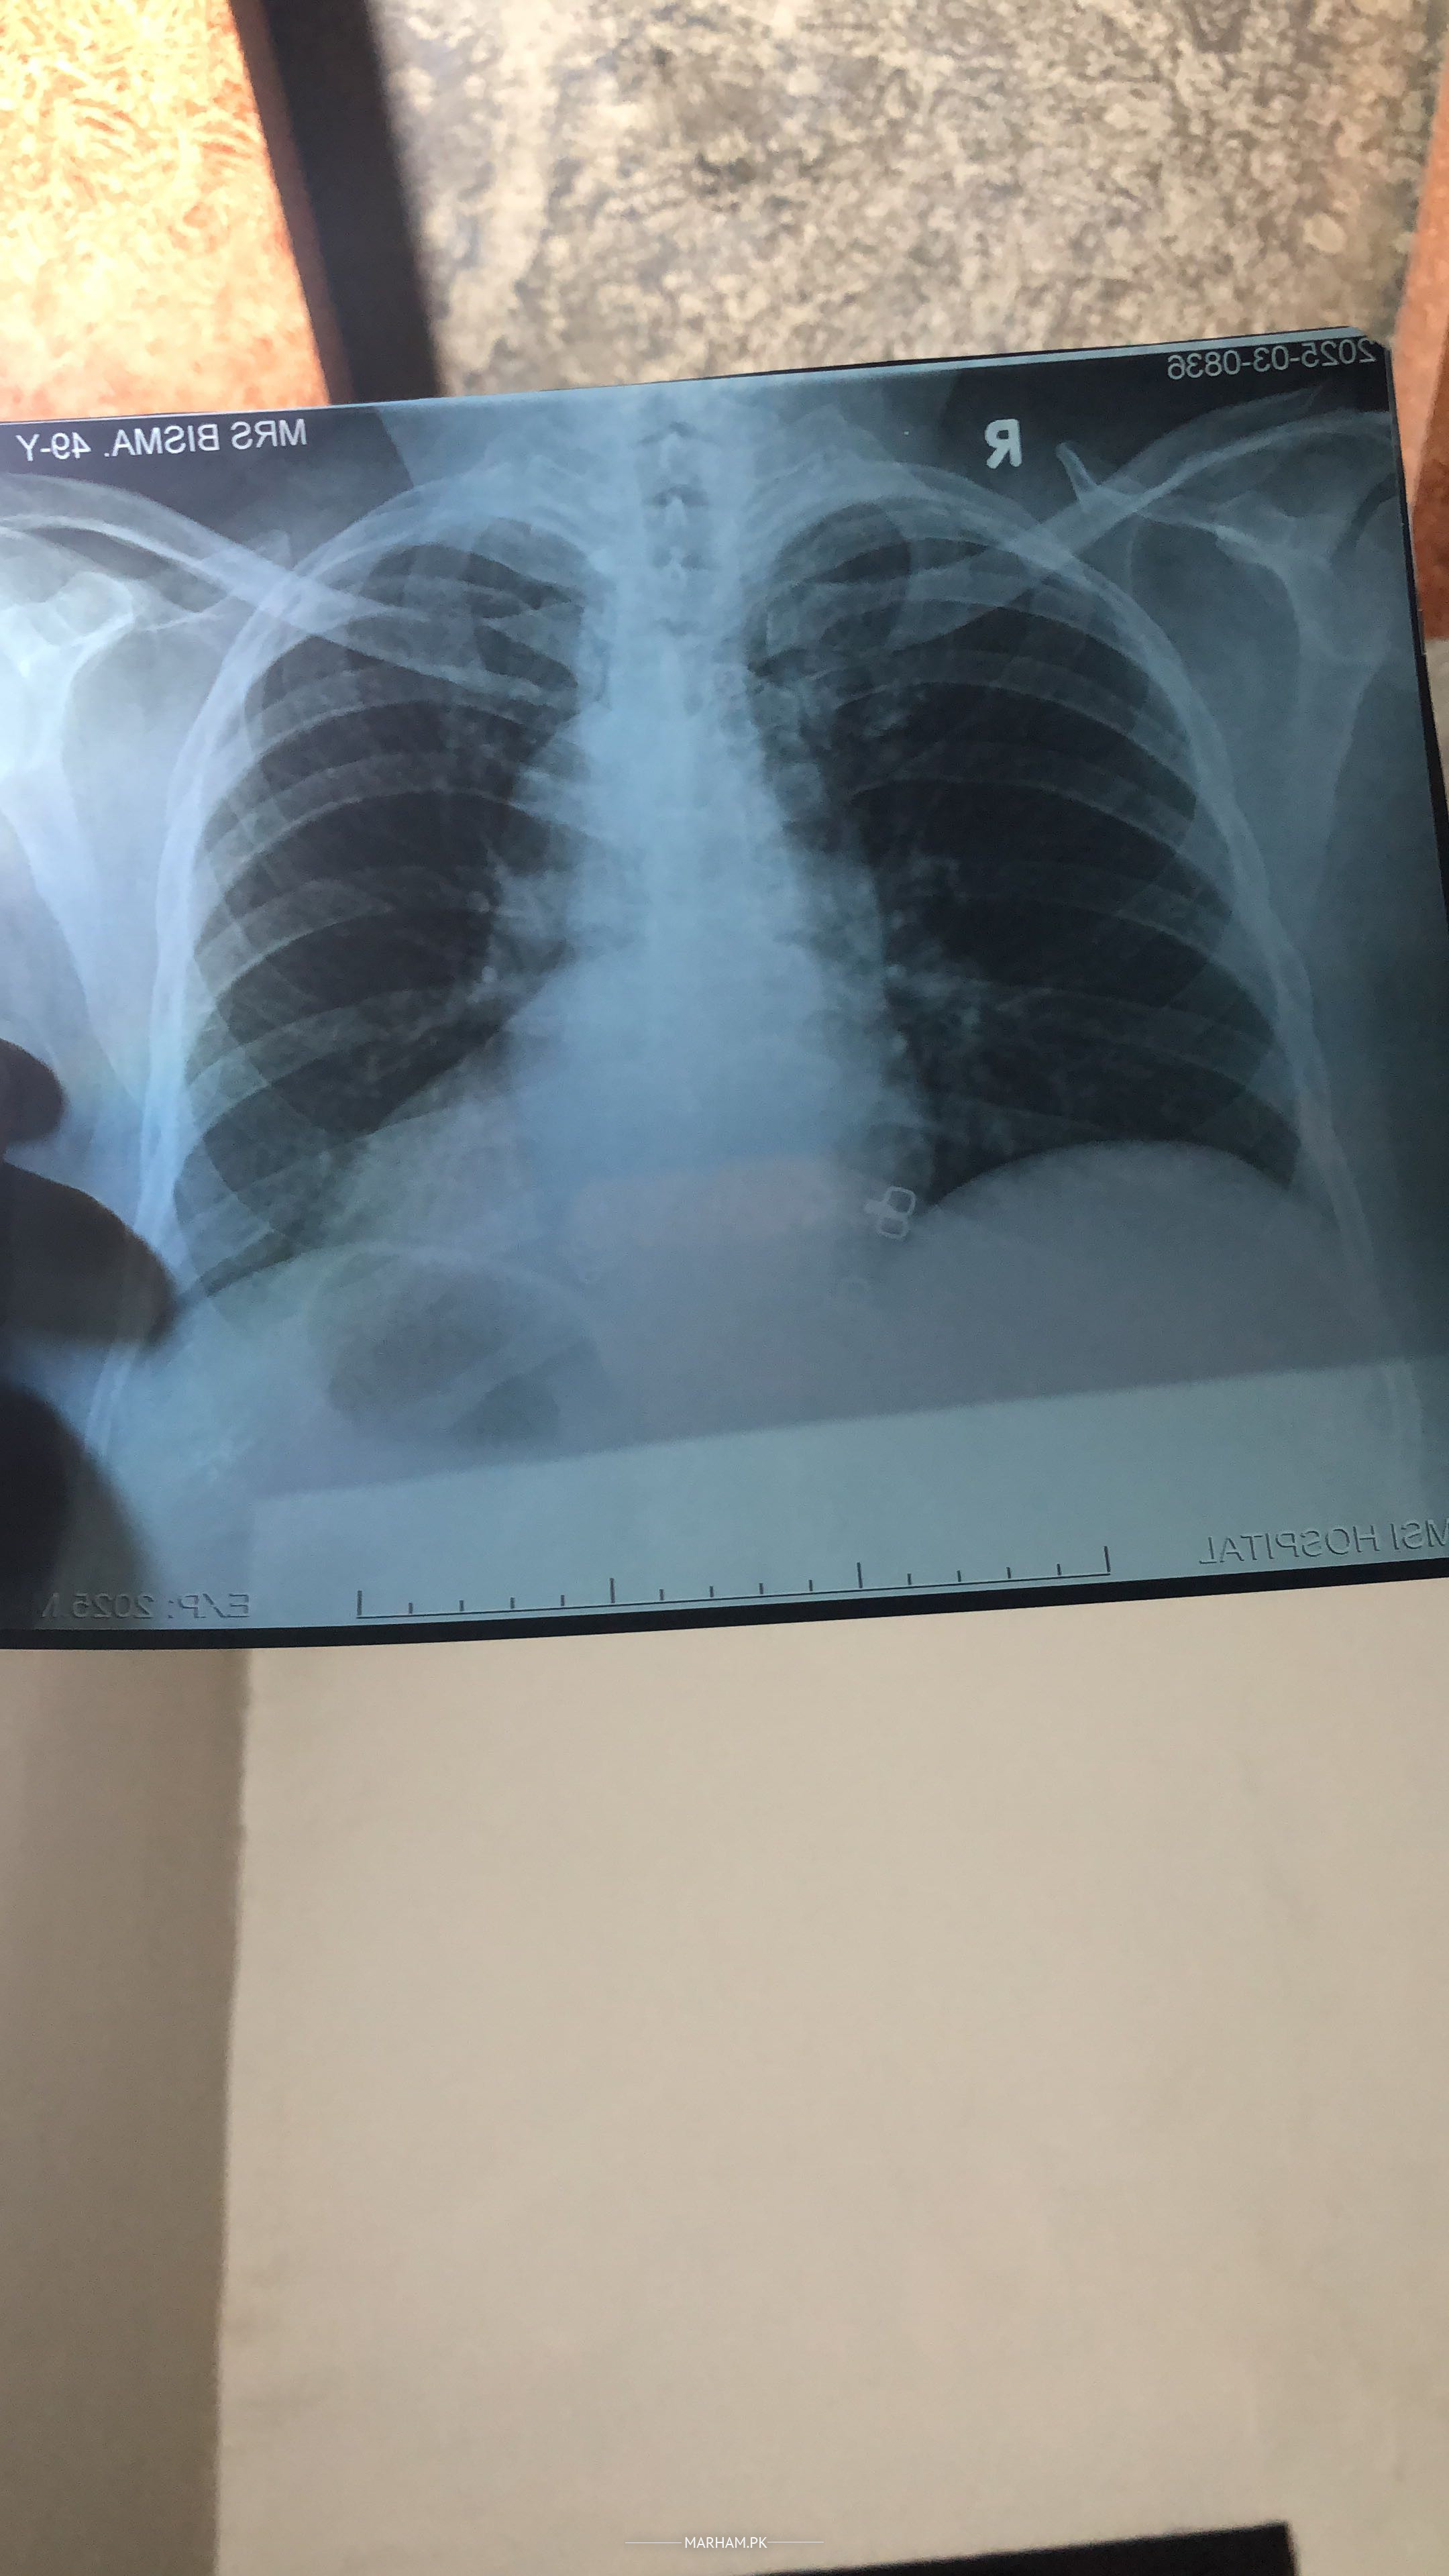

Asking For Someone else, Mother, Female, 54 Years old, Karachi

Please Yh X Ray dekh k baata dein k Yh X Ray Sahi hain?? Please

Ek Bol rhy hain Chest sahi nhi or ek Bol rhy hain k Chest Khrb hai

Plz app bata dein

any history of cough fever in recent days ?

Yes Allergy Asthma hai

than continue medicine for allergic asthma

for proper diagnosis and management need to be visited by a senior general physician specialist

get checked by senior specialist